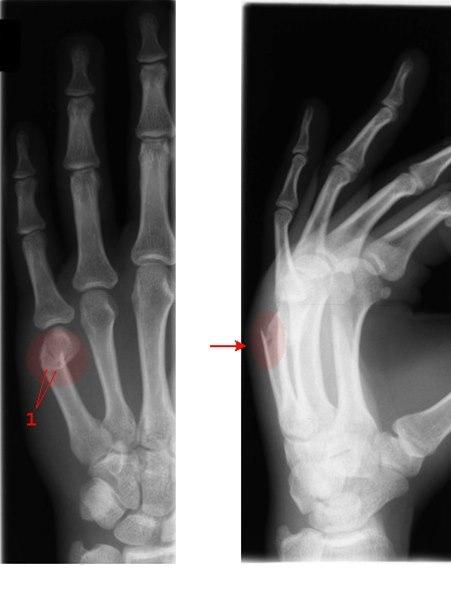

Tverrfraktur femte metacarp (pil)

Typisk fraktur etter slag mot hardt objekt, vegg eller hake